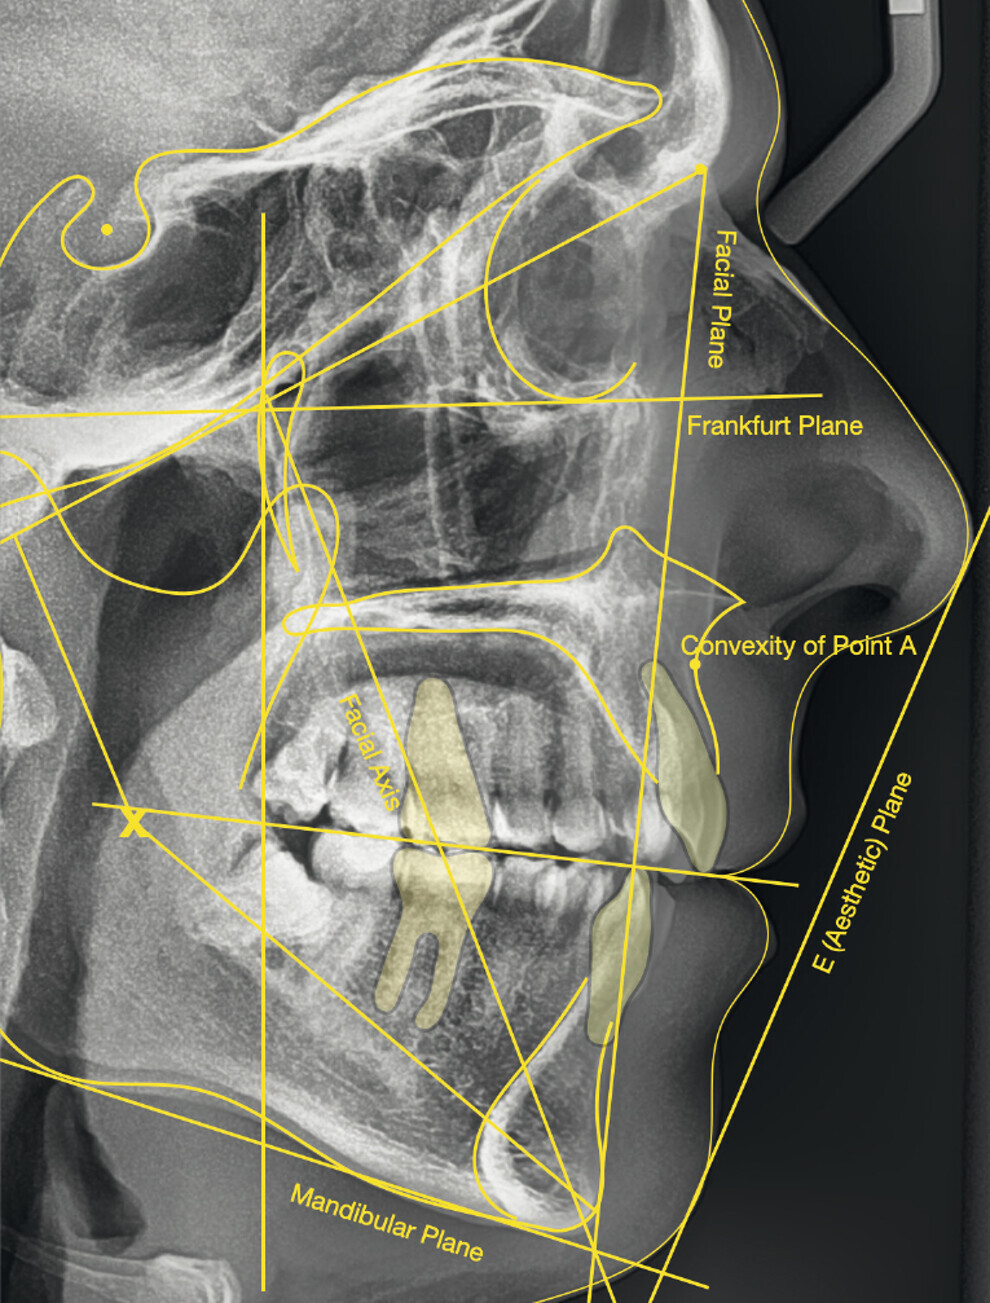

The cephalometric analysis showed a skeletal Class II malocclusion (convexity of Point A: 4.9 mm), a slightly retruded chin position (facial depth: 78.1°) and a skeletal open bite tendency (lower facial height: 53.19°; facial axis: 80.58°; Fig. 9). The mandibular incisors were lingually tipped (Li–APog: 9.3°) and retruded (Li–APog: 1.55 mm), and there was an increased inter-incisal angle of 142.9°.